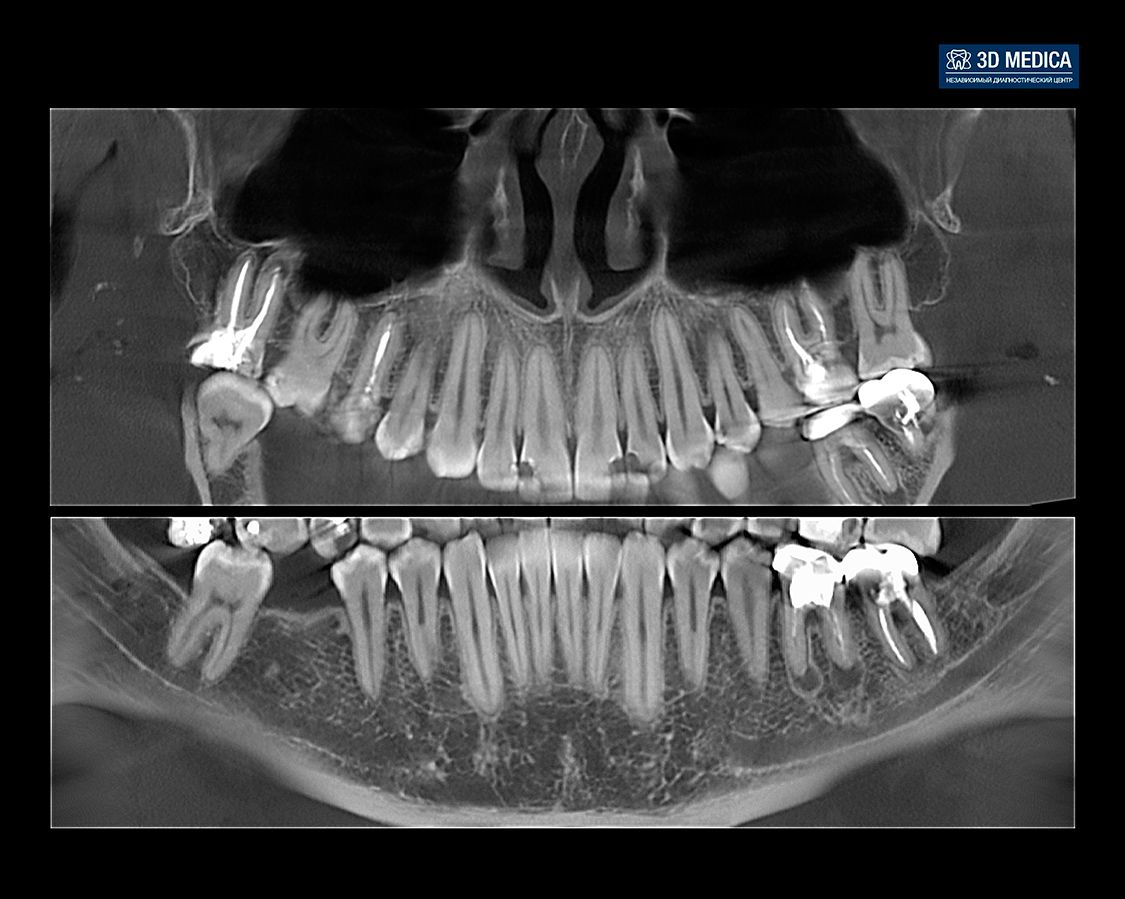

КТ является важным инструментом диагностики в стоматологии, позволяющим получить трехмерное изображение зубов, челюстей и окружающих тканей. Однако, анализ КТ может быть сложным и времязатратным процессом. ИИ помогает автоматизировать и улучшить этот процесс, предлагая ряд преимуществ:

- Автоматическая сегментация: ИИ может автоматически выделять различные структуры на КТ, такие как зубы, кости, нервы и сосуды. Это значительно экономит время стоматолога и снижает риск ошибок;

- Выявление патологий: ИИ может обнаруживать признаки различных патологий, таких как кариес, периодонтит, опухоли и кисты, на самых ранних стадиях. Это позволяет начать лечение вовремя и предотвратить серьезные осложнения.

- Оценка плотности костной ткани: ИИ может точно оценивать плотность костной ткани, что важно при планировании имплантации и других хирургических вмешательств.